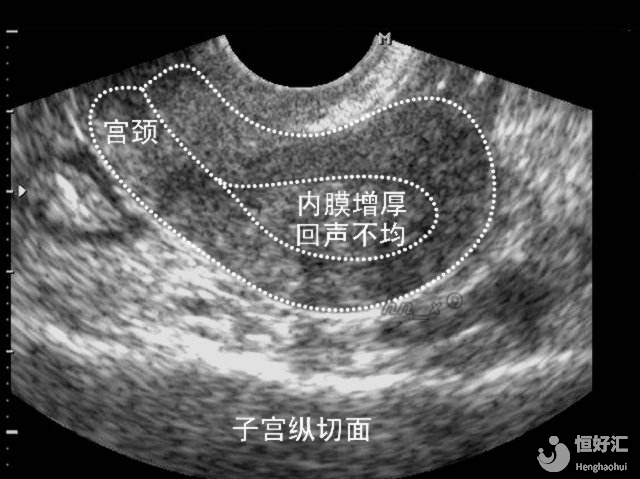

子宮內(nèi)膜并不是越厚越好

子宮內(nèi)膜對試管嬰兒的妊娠成功率確實是關鍵,但并不是越厚就越好的,這個問題本身并不是絕對的。

部分研究認為,子宮內(nèi)膜厚度越厚,那胚胎移植率就會越高;但同時也有一些研究數(shù)據(jù)表示,當子宮內(nèi)膜厚度一旦高于14mm時,胚胎移植成功率是不可觀的。

相反的,如果女性雌激素分泌過多的話,引起子宮內(nèi)膜過度生長,增厚的子宮內(nèi)膜就會脫落從而引起月經(jīng)量過多,容易造成貧血,而且還有可能造成不孕、絕經(jīng)等嚴重問題。